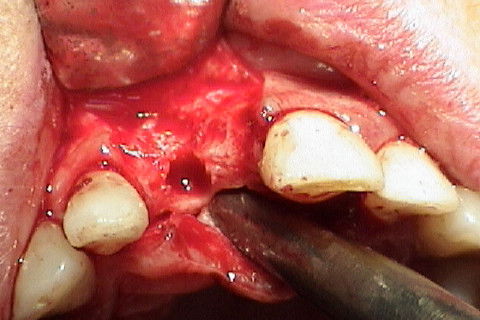

Vista oclusal no momento da reabertura cirúrgica(6 meses após)

Vista vestibular da colocação do cicatrizador com perfil de emergencia